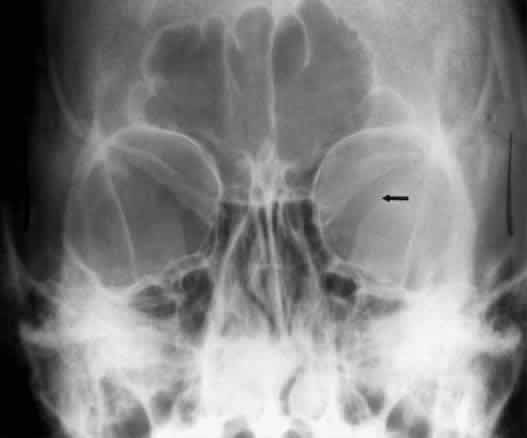

Calcification in the orbit can be seen in retinoblastoma, meningioma, organized hematoma, or a phlebolith associated with venous malformations. Intraocular calcification is seen with tumors such as retinoblastoma or with degenerative changes of the lens, choroid, or vitreous23 (Figs. 10 and 11).

Fig. 10. Caldwell projection of a hemangioma of the left orbit. Soft tissue density is seen in the lateral orbit with partial calcification (arrows).